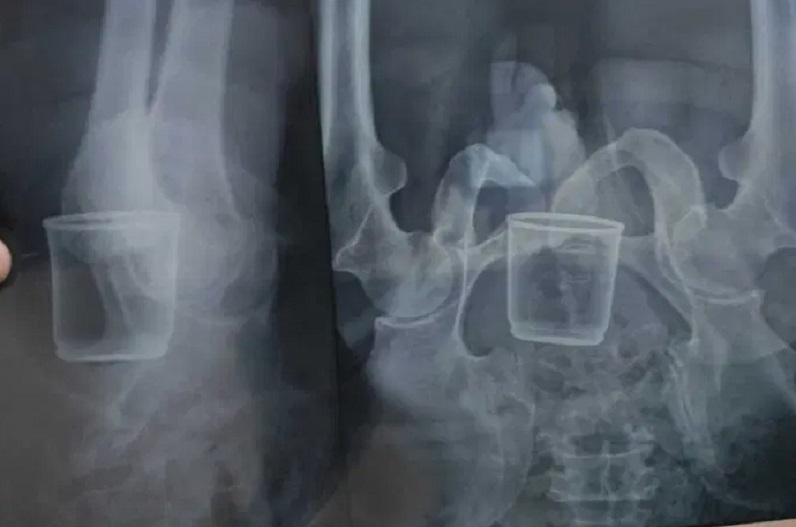

राजगढ़ : Bullies put a glass in private part of the elderly saint : जिले से मानवता को शर्मसार करने वाला एक मामला सामने आया है, जिसे सुनकर आपका भी दिल दहल जाएगा। यहां गांव में पूजा पाठ करने वाले बुजुर्ग संत के साथ दबंगों ने बड़ी बेरहमी से मारपीट की। दबंगों का मन मारपीट से नहीं भरा तो उन्होंने संत को गिलास के ऊपर बैठाकर दबा दिया। इस वजह से गिलास उनके प्राइवेट पार्ट में घुस गया।

Bullies put a glass in private part of the elderly saint : मिली जानकारी के अनुसार करीब 2 साल पहले संत ने गांव वालों के साथ मिलकर गांव में यज्ञ और पूजा-पाठ कराने का फैसला किया था। इसके लिए उन्होंने चंदा भी इकठ्ठा कर लिया था। यज्ञ का आयोजन हो पाता इससे पहले ही कोरोना आ गया और इस वजह से गांव में पूजा नहीं हो पाई। 3 महीने पहले संत उन लोगों के घर गए और उनसे दोबारा पूजा कराने के लिए कहने लगे। इसी बात से नाराज होकर 3 गांवों (अमावता, कछोटिया और हलाहेड़ी) के कुछ दबंगों ने मिलकर उन्हें पीट दिया। पीटने के बाद दबंगों ने संत के प्राइवेट पार्ट में गिलास घुसा दिया।

यज्ञ करवाने की बात पर भड़के दबंग

Bullies put a glass in private part of the elderly saint : 95 साल के पीड़ित संत का कहना है कि यज्ञ के लिए कितना पैसा इकट्ठा हुआ था, ये तो उन लोगों ने किसी को नहीं बताया, लेकिन इतना पता है कि कम से कम सवा लाख रुपये इकट्ठे हुए थे। मैंने उनसे कहा कि अब तो कोरोना खत्म हो गया है, अब यज्ञ करवा सकते हैं। इसी बात से वे लोग भड़क गए और मुझे मारने लगे। इसके बाद उन्होंने मुझे स्टील के एक ग्लास पर बैठा दिया और फिर मुझे दबाने लगे। जिससे वो ग्लास मेरे अंदर चला गया।

3 महीने तक मैं छापीहेड़ा से दूर पिछोर में इलाज करा रहा था। मुझे यहां इलाज करवाने में डर लग रहा था, कहीं वो मुझे जान से न मार दें। दूसरा यहां लोग मुझे जानते हैं, इसलिए यहां इलाज कराने में शर्म भी आ रही थी। हाल ही में जब तकलीफ बढ़ गई और सहन नहीं हुई तो पेट दर्द की बात कहकर ग्रामीणों के साथ राजगढ़ अस्पताल पहुंचा।

Bullies put a glass in private part of the elderly saint : राजगढ़ जिला अस्पताल के सर्जन डॉ. राजेंद्र काठेरिया ने बताया कि हमने पीड़ित के अंदर से ग्लास निकालने की कोशिश की, लेकिन निकाल नहीं पाए। पीड़ित को भोपाल रेफर कर दिया गया है। ग्लास आंतों में पूरी तरह से चिपक चुका है। इसलिए हमने उन्हें भोपाल के हमीदिया अस्पताल में रेफर किया है।